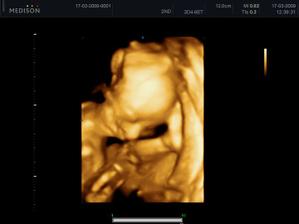

Simonka naše sluníčko koukla na svět 27.7.2009 v 11.24hod Bylo to pondělí a byla na svět přivedena císařským řezem se spinální anestezii.Bylo nádherné vidět dítě hned jakmile opustila pelíšek v bříšku. I tatínkovi ukápla slza když si ji přiložil na holou hruď 😉. Naše štěstí bylo veliké 47 cm a těžké2950g a narodila se o 2 dny později.A jak se naše štěstí vyvíjí můžete schlédnout v albu .......příjemné koukáníčko.